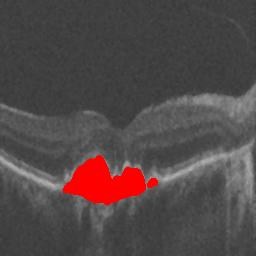

The qualitative results of the proposed system is shown in the Fig. 3. The detection task is evaluated using Area Under the Curve(AUC) metric and the segmentation task is evaluated using Dice Coefficient(DC) metric and the results are presented in Table1

| (a) De-noised OCT slice | (b)Predicted fluid region | (c)Manual fluid segmentation |

| (d) De-noised OCT slice | (e)Predicted fluid region | (f)Manual fluid segmentation |

| (g) De-noised OCT slice | (h)Predicted fluid region | (i)Manual fluid segmentation |

| (j) De-noised OCT slice | (k)Predicted fluid region | (l)Manual fluid segmentation |

| (m) De-noised OCT slice | (n)Predicted fluid region | (o)Manual fluid segmentation |